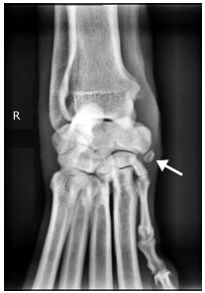

63.9歲拉不拉多犬,右前肢負重跛行,觸診右前肢腕部有觸痛反應,X光影像中箭號處骨樣結構為何? (A)撕裂性骨折(avulsion fracture) (B)碎片骨折(chip fracture) (C)長趾伸肌肌腱(long digital extensor tendon)種子骨 (D)外展拇長肌肌腱(abductor pollicis longus tendon)種子骨